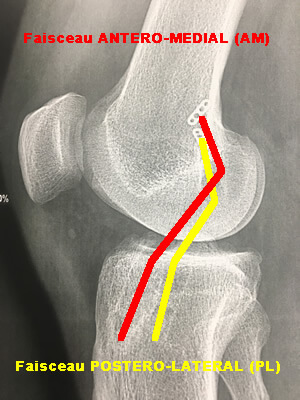

Rupture d'un seul faisceau du LCA

Il s'agit de la rupture de l'un des deux faisceaux du ligament croisé antérieur : antéro médial (AM) et postéro latéral (PL).

Rupture du faisceau antéro-médial

Lorsque le ligament se rompt, c'est d'abord le faisceau antéromédial qui se rompt, entrainant la découverte du lachman lors de l'examen clinique.

Rupture des deux faisceaux

Si la torsion continue, le faisceau postérolatéral se rompt aussi, augmentant le lachman et pouvant donner lieu à un signe de ressaut.

Ces dernières années, de nombreux travaux d'anatomie sur le ligament croisé antérieur ont permis de mettre en évidence que les fibres du ligament pouvaient être regroupées en deux "faisceaux", AM et PL, d'une part par leur position dans l'espace, et d'autre part par des différences dans leur fonctionnement.

Le faisceau AM, rouge sur le dessin,est tendu, lorsque le genou est en extension, tandis que le PL (bleu pale ou jaune) est tendu en flexion.